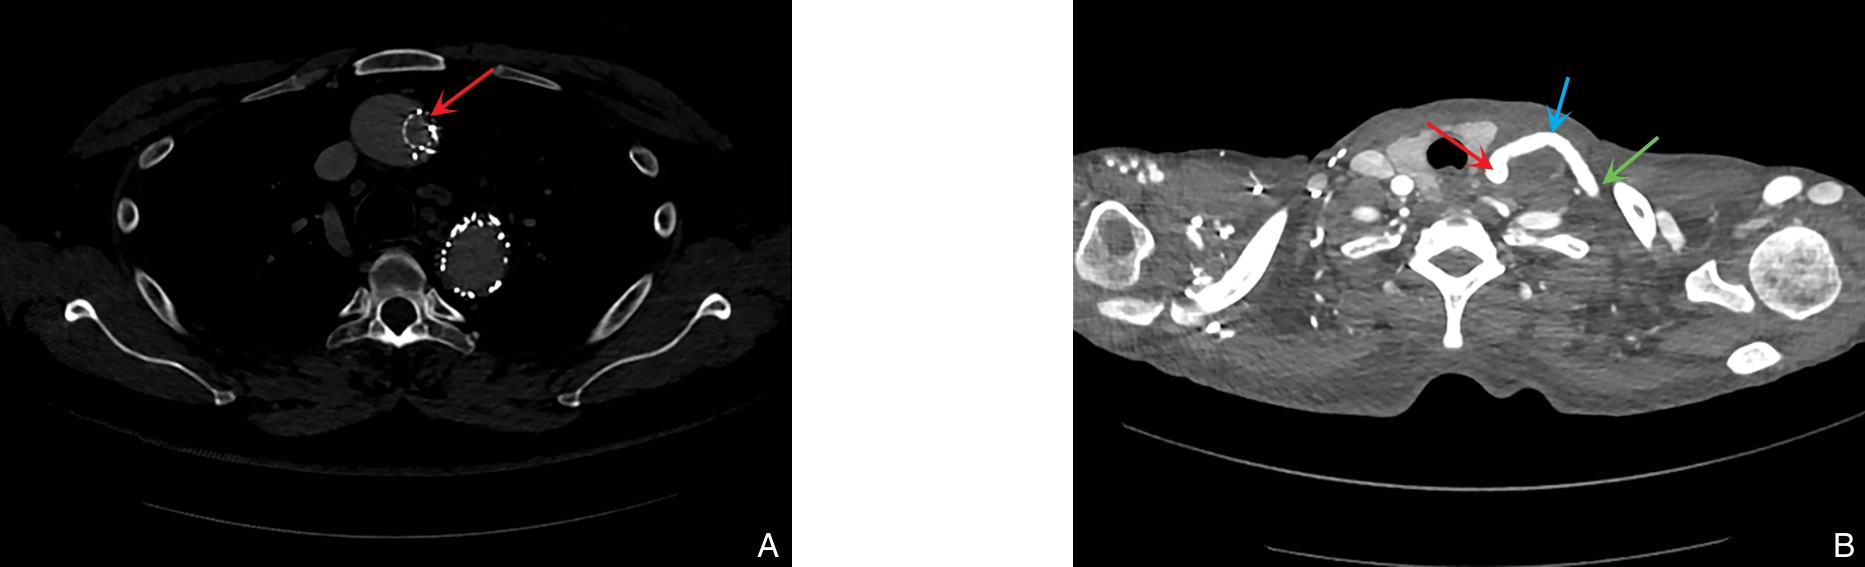

- 不同静脉入路策略在血液透析患者中心静脉狭窄或闭塞腔内治疗中的比较研究